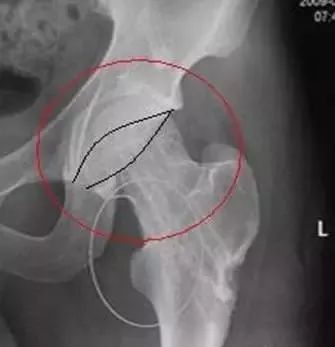

2、Capener征与骨骺滑脱

在儿童髋关节正位片上,股骨颈内侧缘、股骨头骨骺线、髋臼后壁所围成的高密度三角形称之为“Capener征(凯帕诺征)”,当骨骺出现滑脱时,此三角形与健侧对比将变小。